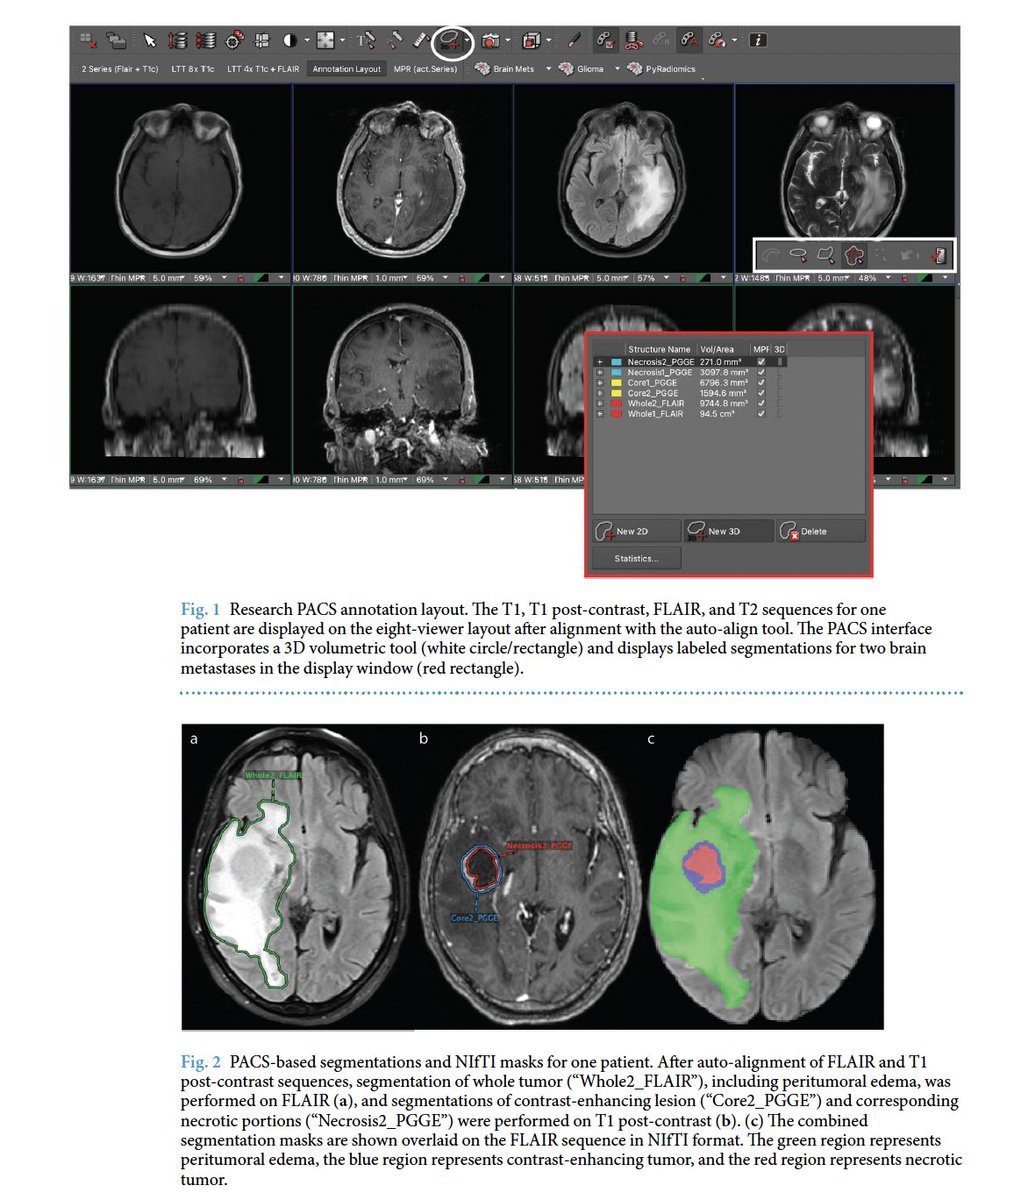

A Large Open Access Dataset of Brain Metastasis 3D Segmentations with Clinical and Imaging Feature Information https://t.co/0jyX0F4ZJY Exciting work led by @DivyaRamakris19 #ImagineQuant #OpenScience #BrainMets @BraTS_challenge #segmentation #collaboration #radtwitter

(2/2) ..don’t forget that you can still review the scientific abstracts on #Whova among which is also our work on PACS-based autosegmentation of brain metastases (BM) and ML-based BM classification. Grateful to have a mentor like @MariamAboian to make work like this possible 🙏